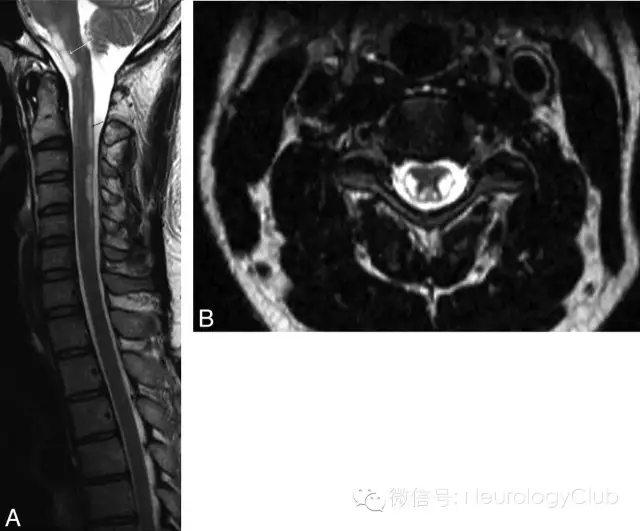

47岁男性,既往有义齿霜使用史,隐匿起病,4周时间逐渐出现双侧无痛性视力丧失,感觉异常和四肢轻瘫。神经系统查体提示左侧瞳孔传入障碍和视神经炎,左侧上运动神经元型面神经瘫痪,四肢轻瘫,反射亢进,下颌反射活跃,T6水平以下各种类型感觉缺失或减退。颈髓(图1)和头颅(图2)MRI如下。

(图1:A:脑干和颈髓矢状位可见锥体束和后索的T2高信号[黑箭],累及脑干[白箭];颈髓横断面可见皮质脊髓侧束和后索对称性T2高信号。胸髓MRI未见明显异常[图未提供])